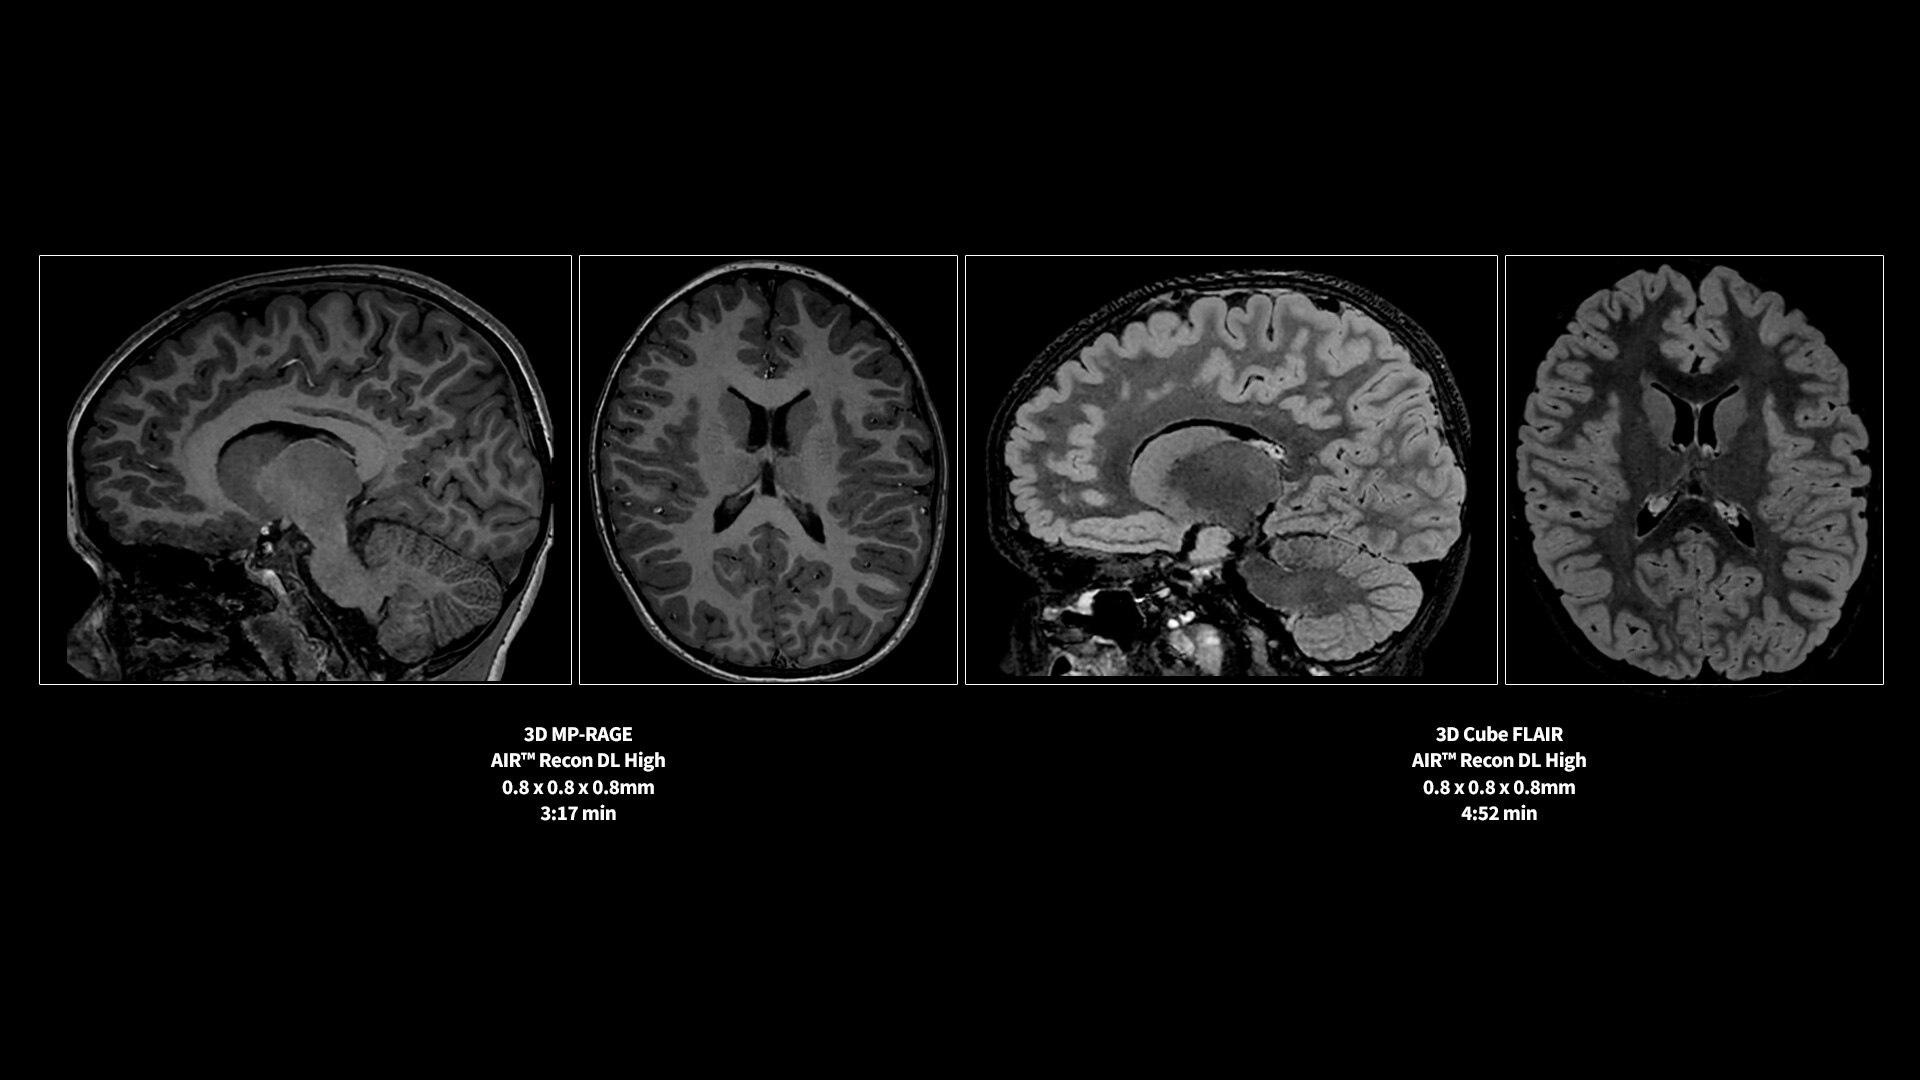

AIR™ Recon DL has revolutionized MR imaging with deep-learning based image reconstruction increased image quality, reduced scan time and improved SNR.